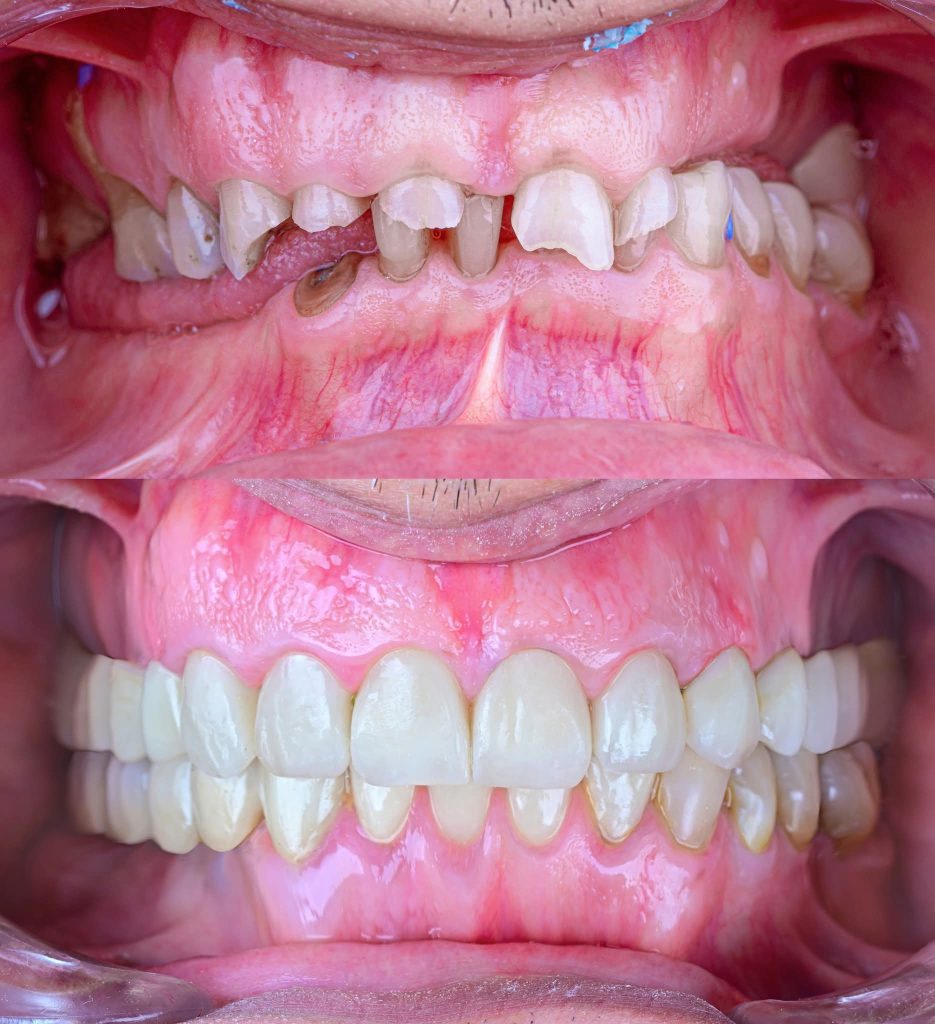

I am revisiting this Full Mouth Rehabilitation case, which was my first published case in this group.

The case was transferred to a semi-adjustable articulator, where the vertical dimension was increased by 5 mm. A diagnostic wax-up and removable prostheses were created at the new vertical dimension, guided by the curve of Spee using Broadrick’s Occlusal Plane Analyzer. Silicone indices were fabricated for both arches.

The patient has now been under follow-up for nearly 4 years and remains very happy and comfortable.